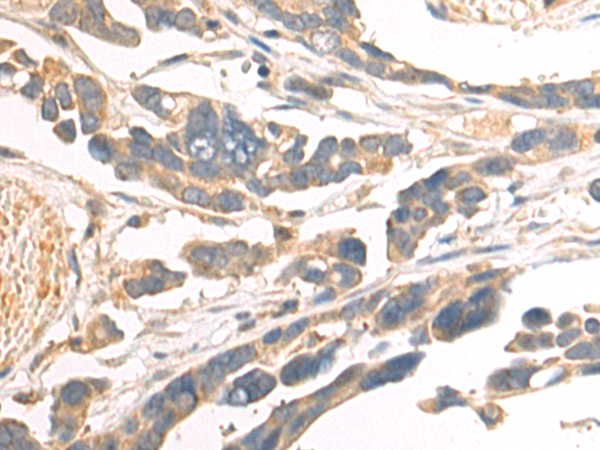

分类: 科研抗体货号: P07679别名: RNF84; MGC:39780应用: IHC反应种属: Human, Mouse